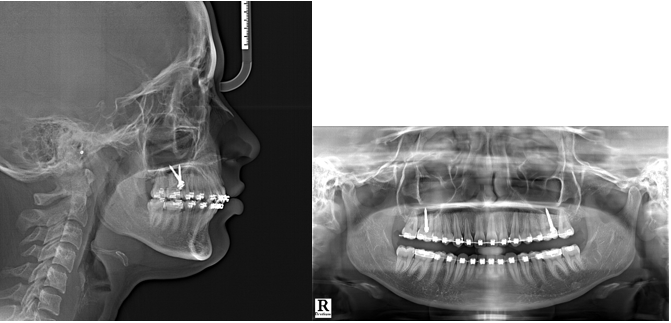

Extraction was performed for teeth 18 and 28, followed by the placement of bands on the first molars in maxilla and mandible, along with the attachment of bonded buccal tubes to second molars in maxilla and mandible. The Damon 0.022" × 0.028" slot metal bracket system by Ormco was utilized. Following the initial phase of leveling and alignment, 19 × 25 stainless steel archwires were introduced in maxilla and mandible. Additionally, 2 stainless steel IZC bone screws (Model: A1P-212012) measuring 2 × 12 mm by Bio-Ray® were strategically positioned in the zygomatic crestal bone in between the first and second maxillary molars on both sides, inclined at an angle of approximately 70 degrees and positioned 9 mm above the cemento-enamel junction.

A figure-of-eight steel ligature wire was employed to create a unified structure spanning across all maxillary teeth, ensuring even distribution of applied forces. A hook of medium-length (8-10mm) was secured on both sides of the maxillary archwire placed distally to the canine. This hook was then connected to the IZC bone screw with a 5mm-long Elastomeric chain, applying a force of 300 grams (10 oz) for distalization (Figure 4, 5).

Taking into account the biomechanical implications, careful attention was given to maintaining the force vector's direction and height at or above the Cres of the maxillary dentition. This strategic approach aimed to induce bodily displacement along with rotation in counter-clockwise direction of the entire dentition and skeletal base. The treatment progressed for a period of 9 months; but as the patient had to relocate permanently to other location she had to regrettably discontinue the treatment. However, the treatment outcomes attained until this juncture have been thoroughly recorded in the following section detailing the results.